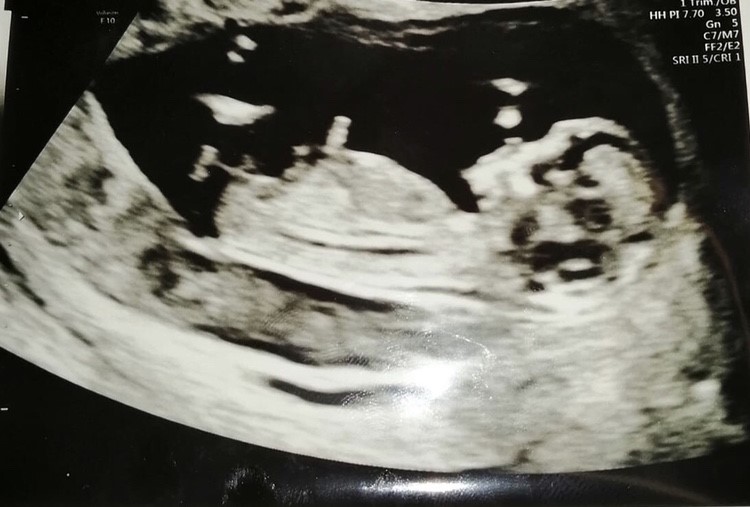

Jeg var i går til Nakkefoldscanning 12+2 og det hele gik lige præcis som at det skulle så fint, og ingenting at komme efter, en rigtig lille sprællerbasse

Jeg står og har købt mig en kønsscanning her d. 20 og jeg kan ikke være i mig selv af spænding. 14+0.

Jeg ved at man intet kan se som sådanne før 14 og frem, men det kunne være sjovt om nogle havde et bud for hyggens skyld?